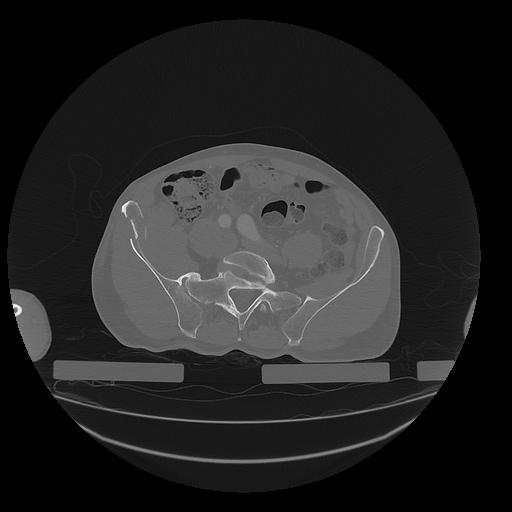

31 PULMON,CE,Vol,1.0,PULMON,,